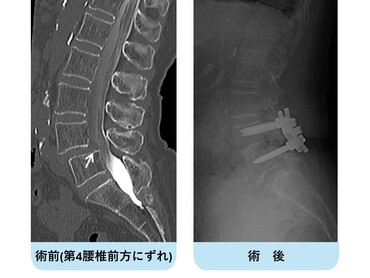

第4腰椎の前方へのすべりのため神経の圧迫を認めています。腰椎後方からずれを金属で整復固定し神経症状が改善しています。